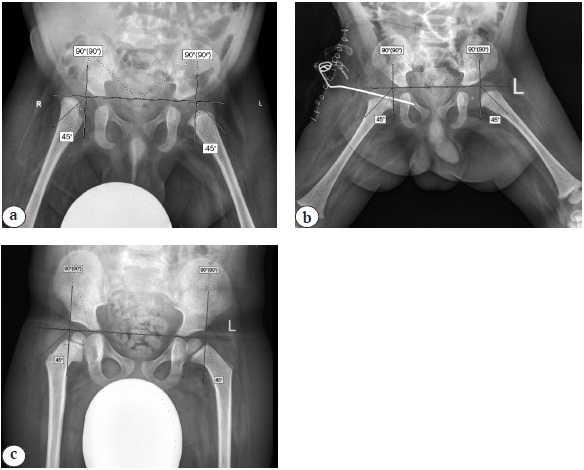

У детей вторых подгрупп после операции ОВБ хорошие результаты отмечены в 17 случаях (90%), удовлетворительные — в 2 наблюдениях (10%), а после ОВБ, КОБ, ПОС хорошие результаты отмечены в 12 наблюдениях (75%), удовлетворительные — в 3 случаях (19%), в 1 наблюдении (6%) получен неудовлетворительный результат (рис. 7).

Рис. 7. Рентгенограммы таза в прямой проекции пациента 7 месяцев из второй подгруппы: a — до операции; b — интраоперационная рентгенограмма после ОВБ; c — через 3,5 года после ОВБ / Fig. 7. X-ray of the hip joints in the A–P view, in a 7-month-old patient subgroup 2: a — before surgery; b — intraoperative X-ray after hip open reduction; c — 3.5 years after surgery